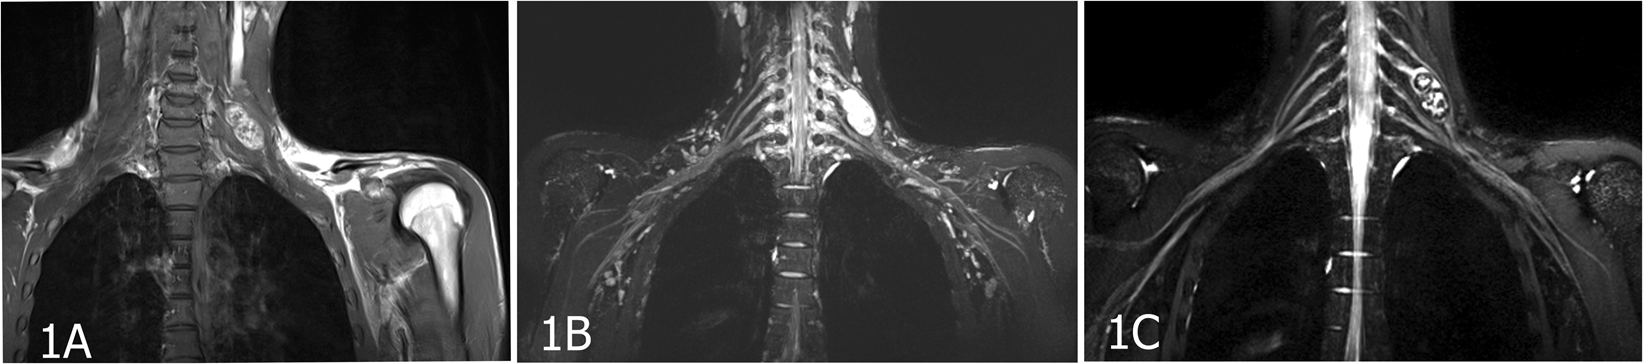

Figure 1

An 18-year-old male patient with peripheral nerve sheath tumors in the left C6 spinal nerve. (A) The lesion in the left neck was well circumscribed with inhomogeneous enhancement on coronal enhanced T1WI. (B) Coronal MIP 3D-STIR SPACE image shows inhomogeneously enhanced mass closely related to the left C6 nerve and pushing the left C5 nerve. (C) Compared with T1WI image, contrast-enhanced 3D-STIR SPACE image has better effect of background suppression, the mass was originated from C6 nerve.